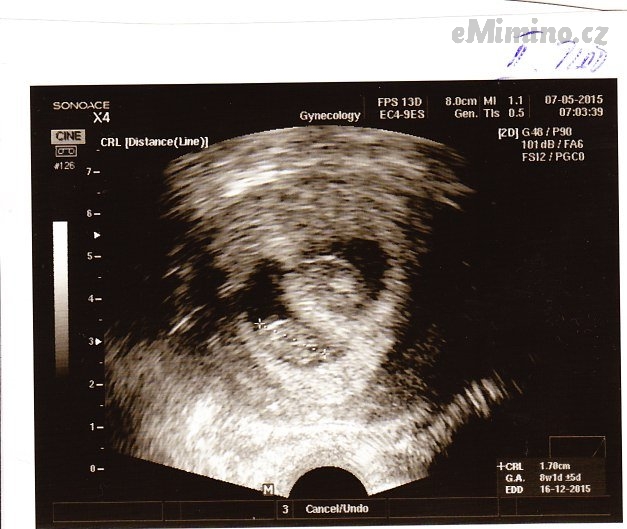

7. května 2015 (8+4)

– první miminko 8+1, 1.95cm

– druhé miminko 8+1, 1,73cm